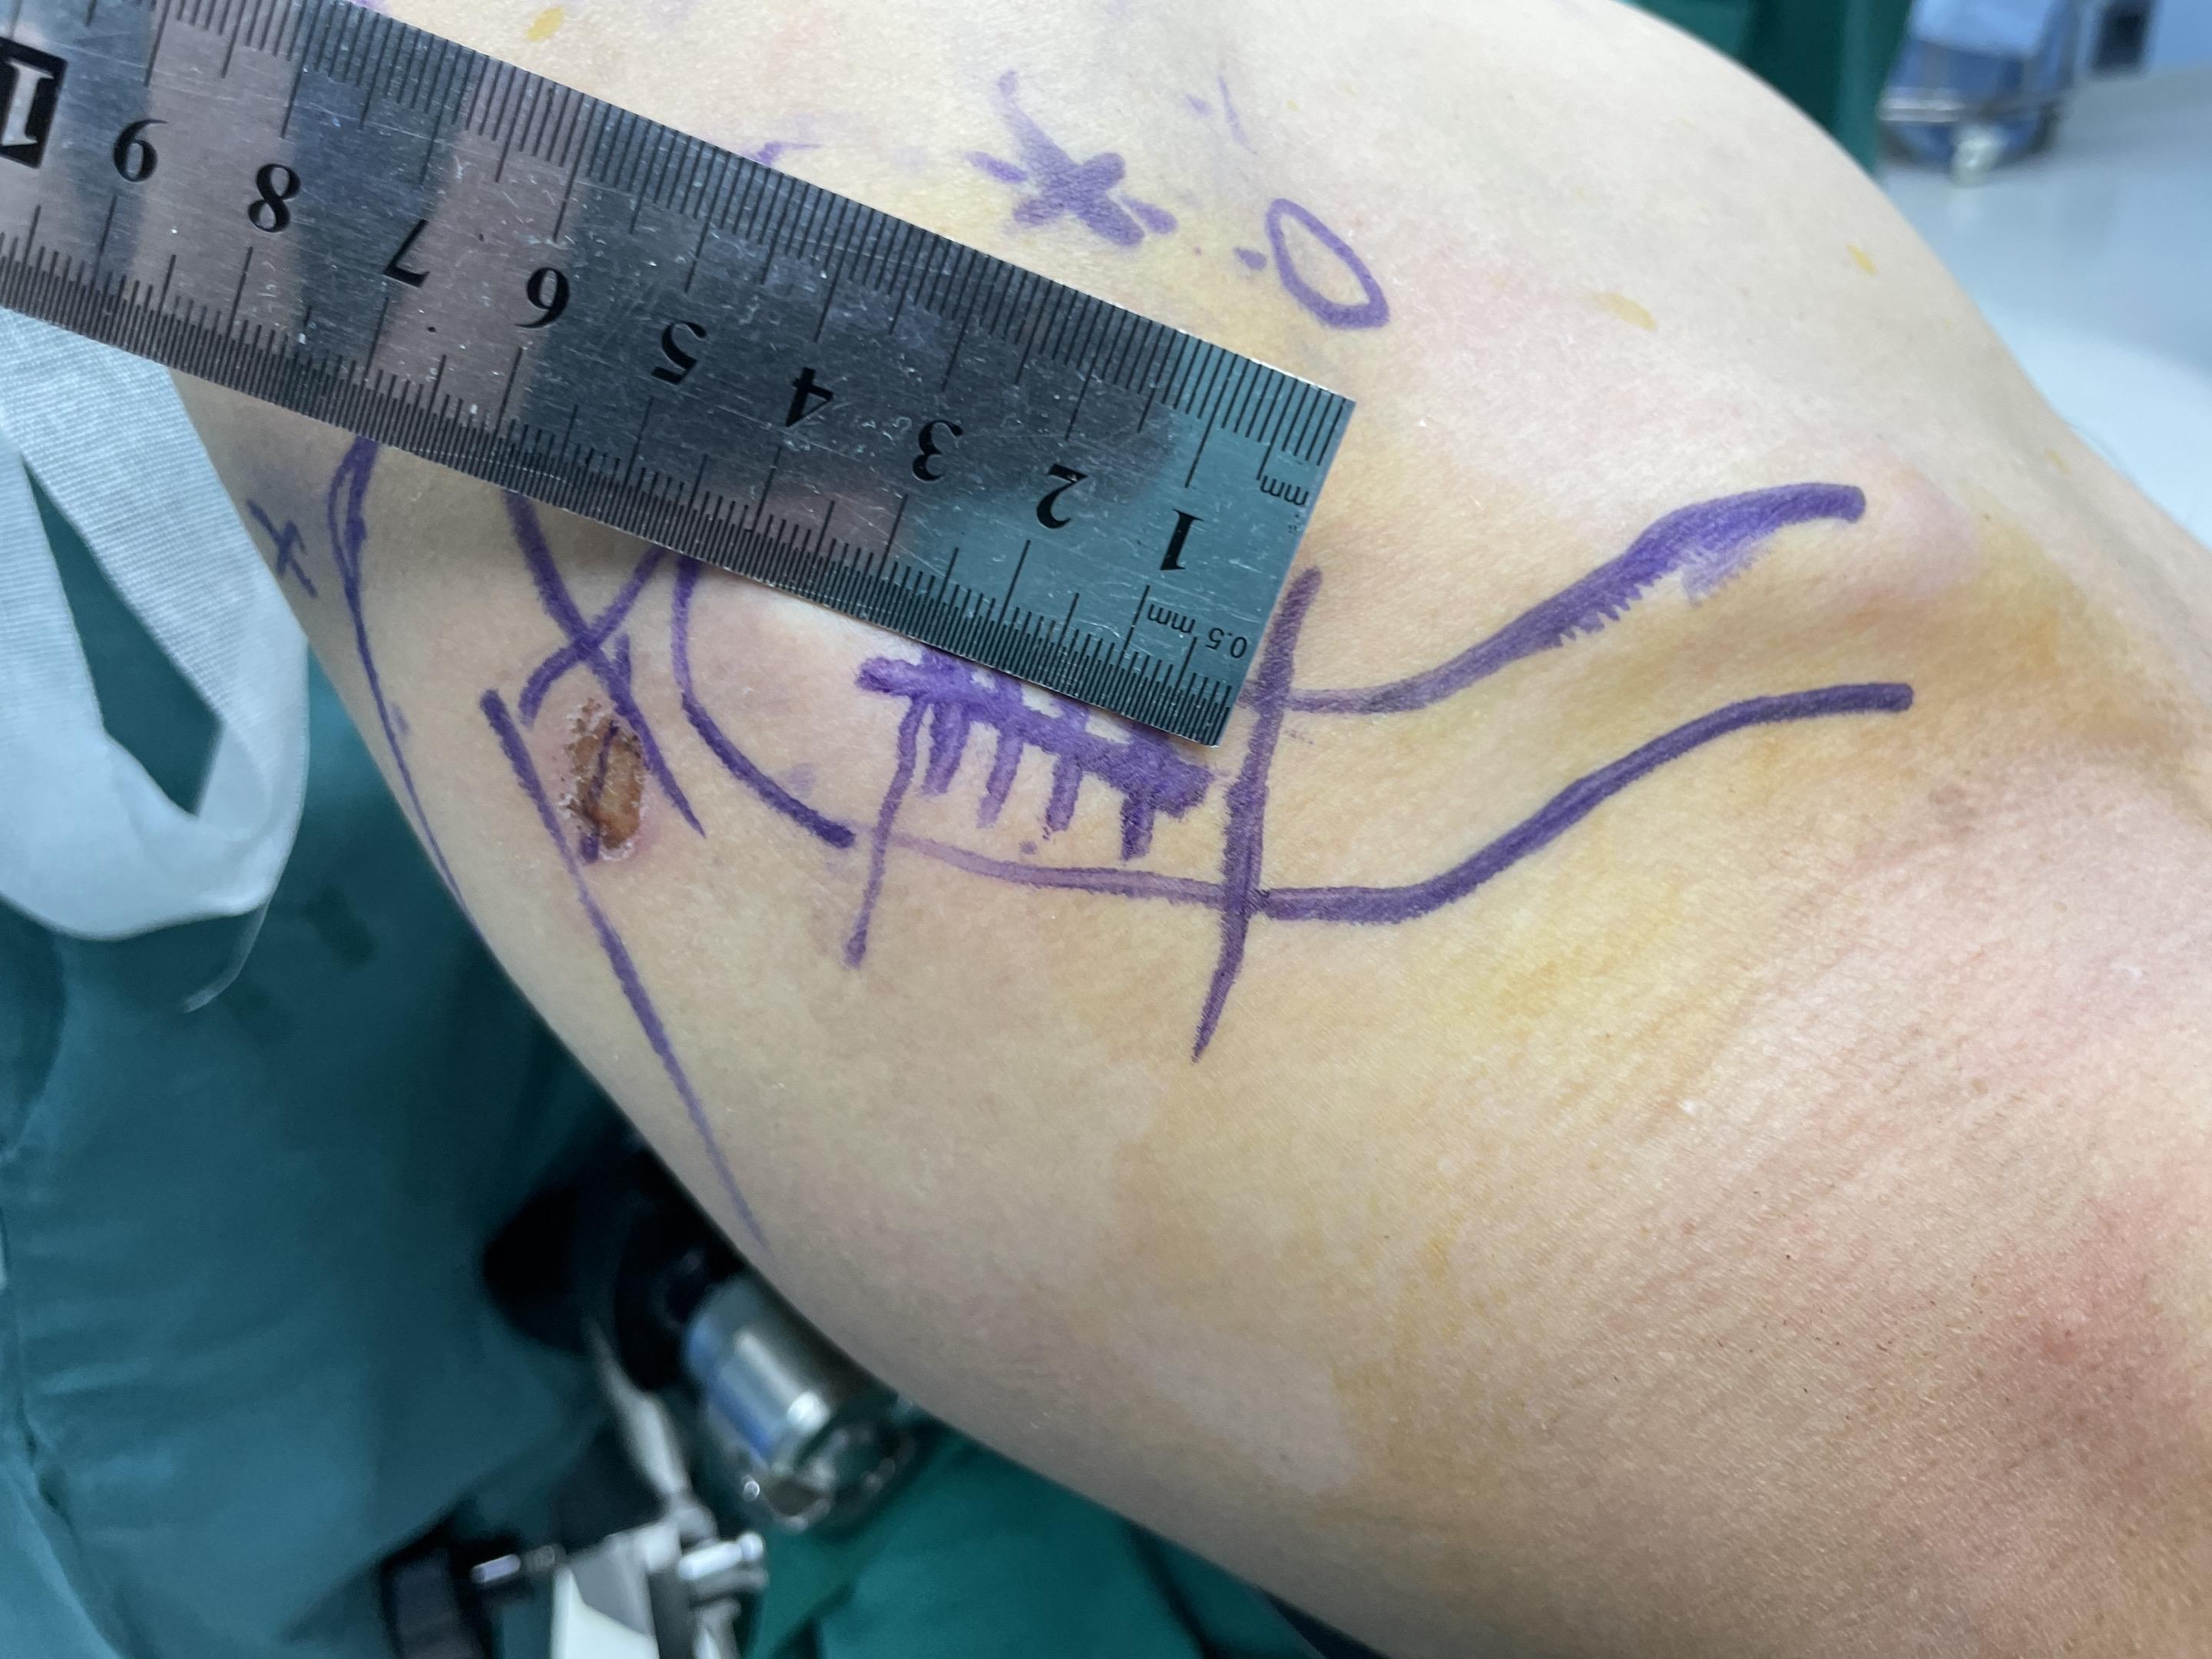

肩锁关节脱位。手术台上的每一次突破,都离不开前辈的倾囊相授。感谢赵立连主任的悉心指导,从理论到细节。